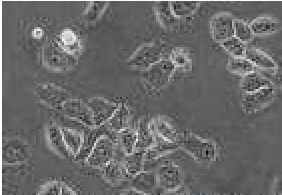

特徵特性:分解酪素和次黃嘌呤;不分解腺嘌呤、尿素或黃嘌呤。10℃不生長;28—40℃生長;50℃存活8小時。還原硝酸鹽。少數菌株對溶菌酶敏感。水解七葉樹素和澱粉。從葡萄糖、阿拉伯糖、木糖、鼠李糖、海藻糖和側金盞醇產酸;從蜜二糖、棉子糖、山梨醇和赤蘚醇不產酸。利用檸檬酸鹽、琥珀酸鹽和蘋果酸鹽,分解酪氨酸。在貝氏瓊脂和土壤浸汁瓊脂里,菌落絲狀。約一半菌株產生氣絲。其中少數菌株氣絲長,有圈卷側枝,斷裂為短孢子鏈;大部分菌株氣絲稀疏。菌落平坦或皺、褶疊,微白色,有粉紅斑點或本色,菌落紅橙色。一些株產生褐色,另一些產生絳紅色可溶色素。從土壤分離出來的菌株與其他來源的菌株無區別。

描述孢子絲彎曲;孢子橢圓形、長圓形;不產H2S;不產類黑色素;明膠液化快;纖維素上不生長;牛奶凝固且腖化;細胞壁含內消鏇二氨基庚二酸以及葡萄糖和甘露糖。

特徵特性孢子絲彎曲;孢子橢圓形、長圓形;不產H2S;不產類黑色素;明膠液化快;纖維素上不生長;牛奶凝固且腖化;細胞壁含內消鏇二氨基庚二酸以及葡萄糖和甘露糖。